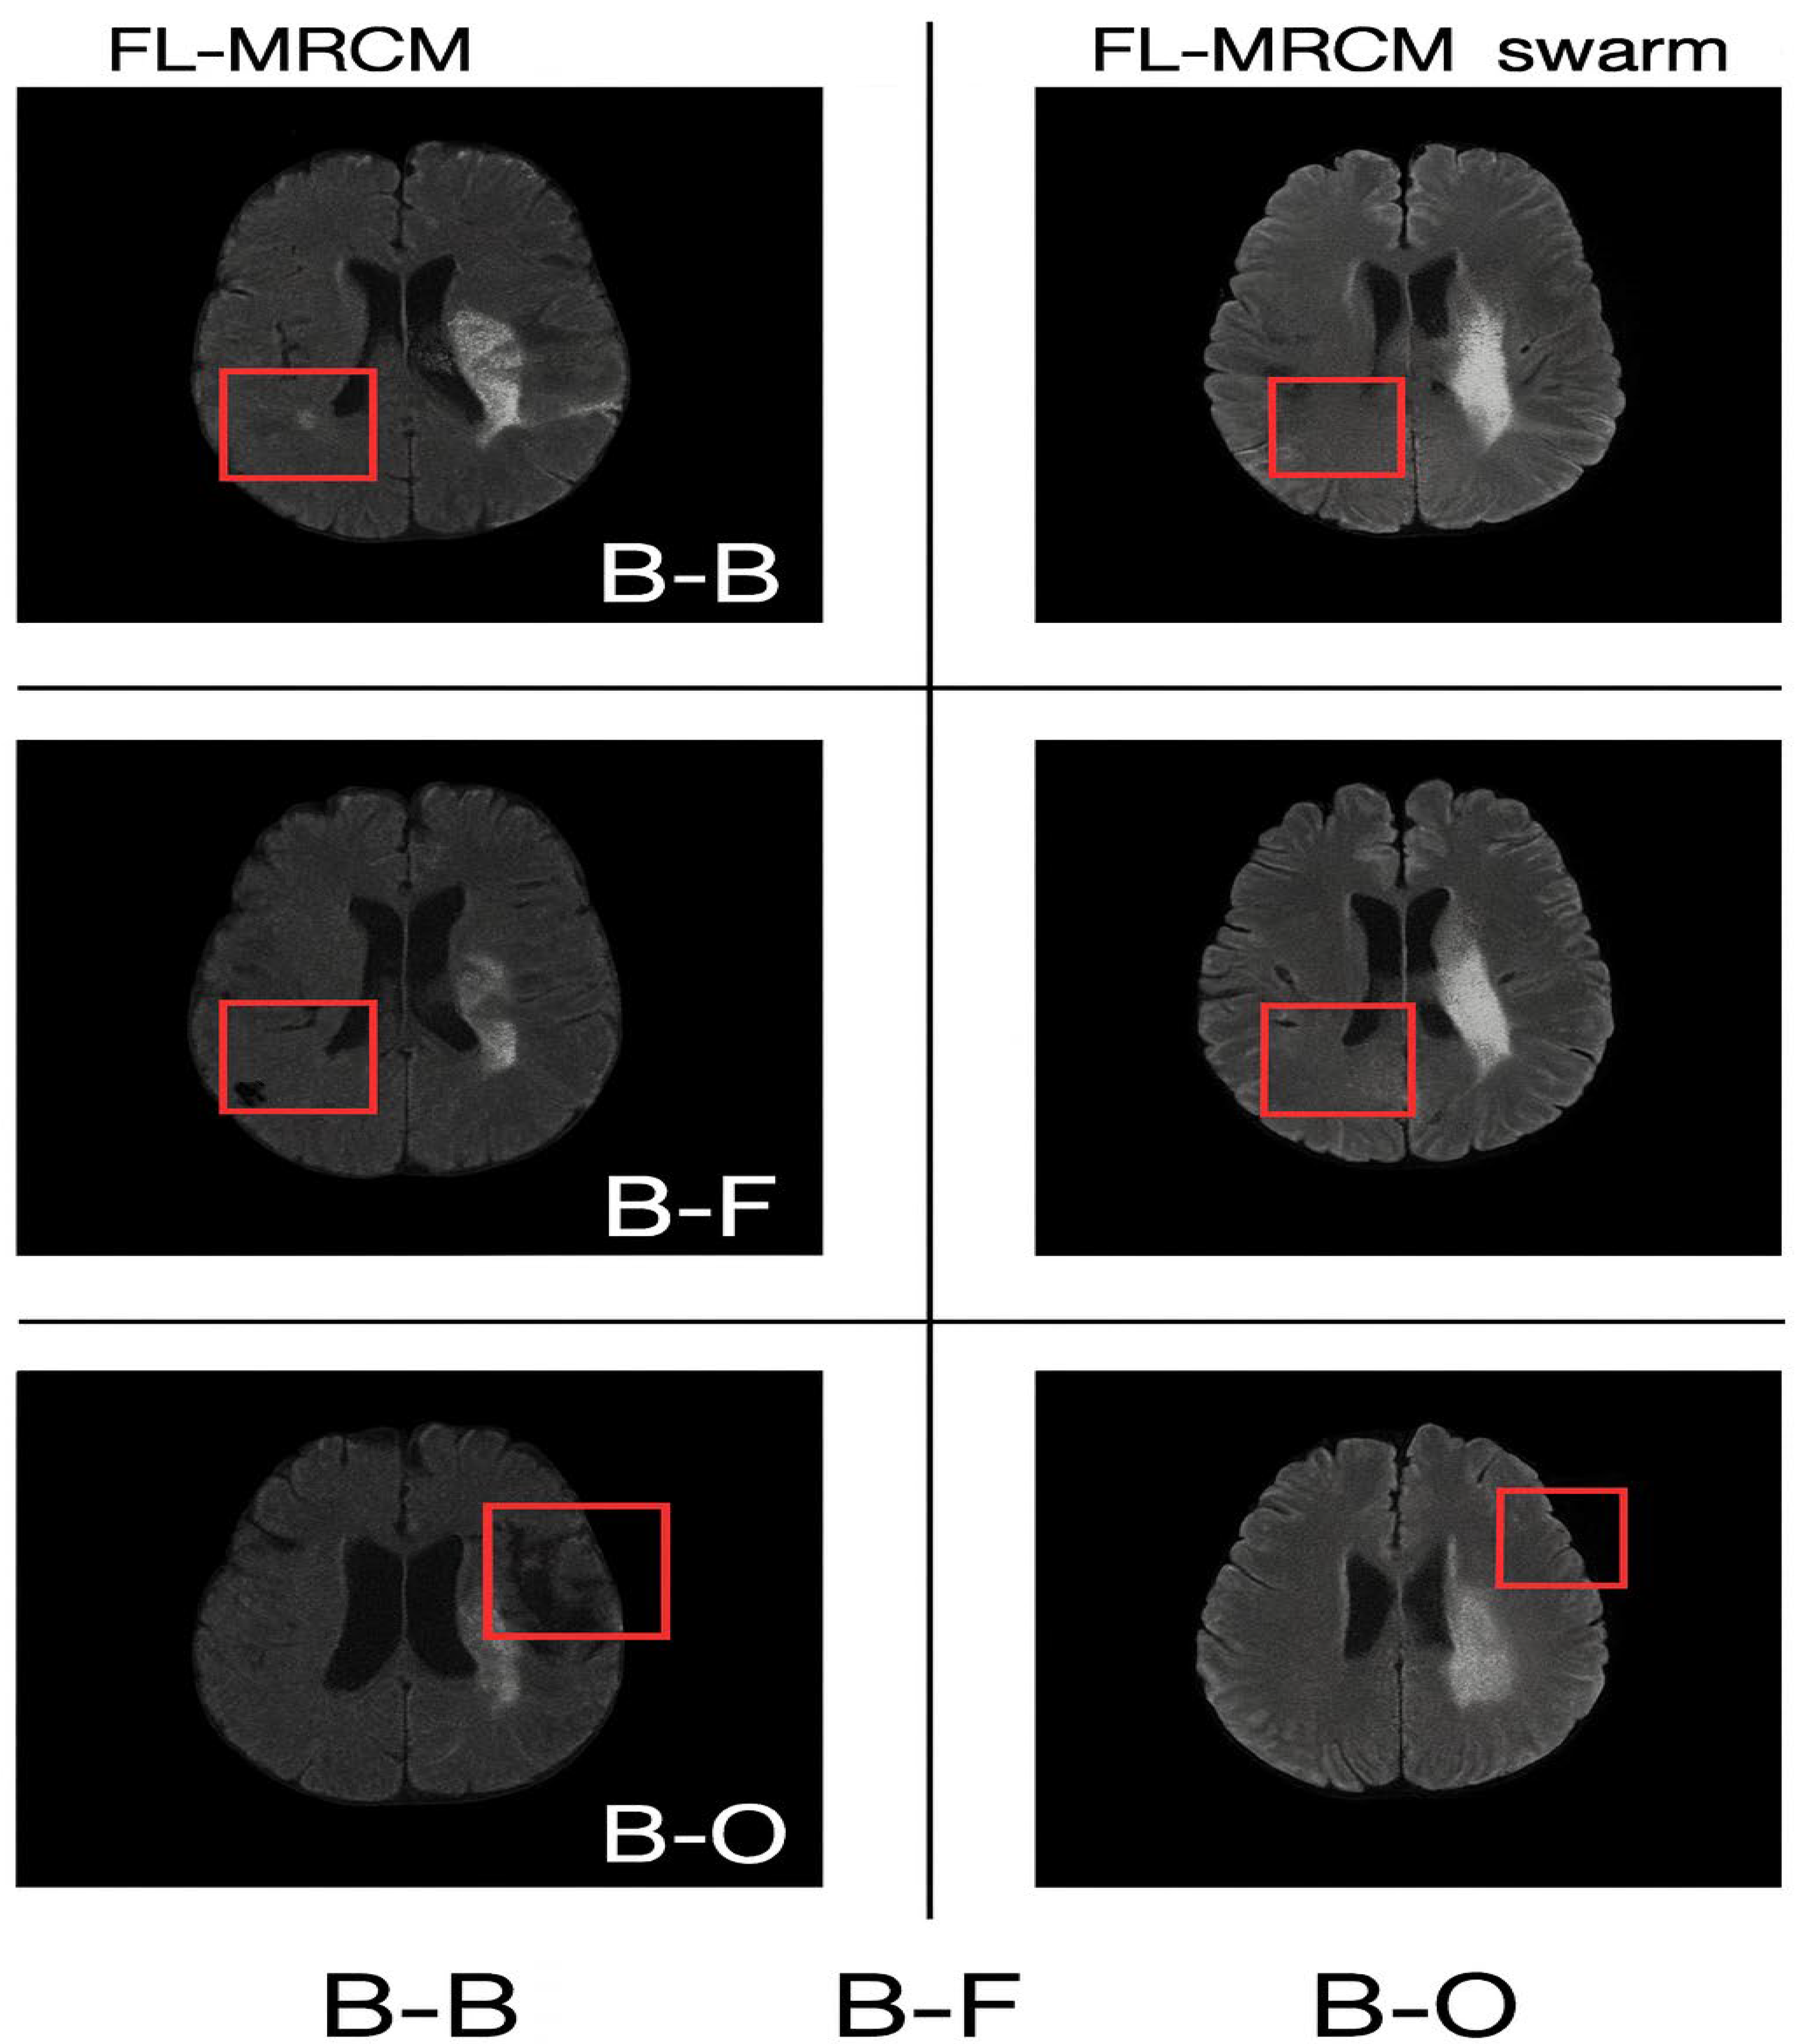

Detailed ablation studies were conducted to analyze the efficiency of the proposed methodology. Here, a trained model was obtained from one of the sites (institutions) and evaluated against data from another institution. The performance metrics obtained after executing the FL algorithms are tabulated in Table 5. It is clear from Table 5 that the proposed FL-SwarmGAN MRCM outperforms, exhibiting better collaborations and generalizability. It clearly improves the reconstruction image quality in every dataset as shown in Figure 11 and Figure 12. The qualitative reconstruction comparisons for cross-site scenarios (B-B, B-F, and B-O) are presented in Figure 11. This figure illustrates the visual differences between FL-MRCM and FL-MRCM-Swarm across varying institutional configurations. The red boxes highlight the regions of interest used to visually assess reconstruction differences between the methods.

The qualitative reconstruction results for cross-site scenarios B–B, B–F, and B–O generated using FL-MRCM and FL-MRCM-swarm are shown in Figure 12. These visual examples highlight method-specific differences in anatomical preservation and artifact suppression.